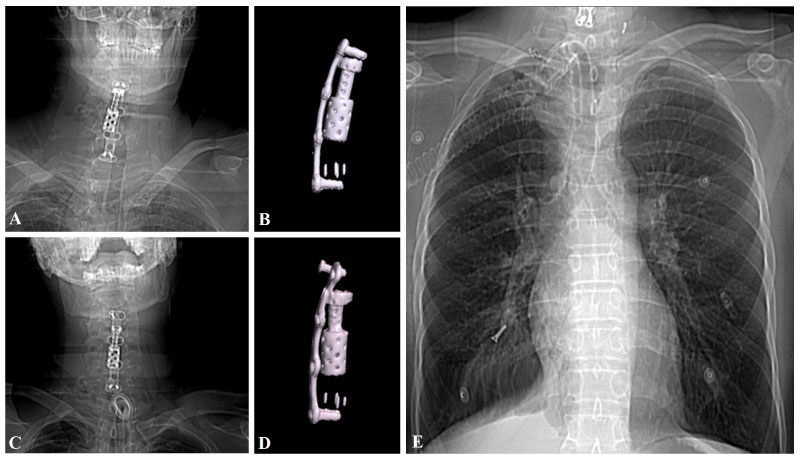

A 44-year-old male patient was admitted to the emergency department for spinal cord injury after a motor vehicle accident. His neurological examination revealed tetraplegia. Spinal radiological imaging revealed diffuse spinal cord edema (Figure 3A) and 2 mm epidural collection at C3-7 levels. Hemodynamic stabilization of the patient who has a spinal shock state was provided in the neuro-intensive care unit. C4-5 corpectomy and C6-7 discectomy were performed urgently to provide spinal decompression. The fusion was achieved using a distractible cage and a PEEK cage (Figure 3B). Anterior plate stabilization was performed (Figure 4A and Figure 4B). The patient's follow-up and treatment continued in the neuro-intensive care unit with the support of mechanical ventilation. Two months after the operation, a screw was detected in the right lung distal bronchus in the routine PA chest X-ray (Figure 4E). Spinal imaging revealed that the upper left screw which was fixed to the C3 corpus was not in place (Figure 4C and Figure 4D) and that it had migrated to the thoracic cavity after creating a perforation in the pharyngeal wall. The patient underwent rigid bronchoscopy, and the screw was removed. Upper fixation screws were revised and stabilized surgically. Since the patient had a tracheostomy and receives the enteral tube feeding, the pharyngeal perforation was left to secondary wound healing. The patient was referred to the physical therapy center after three months from the operation.

Loosening of the screws and/or plates used in surgery and their migration may cause chronic irritation in the posterior wall of the pharyngoesophageal cavity [3]. This may cause inflammation, focal ischemia and necrosis, cellulite, formation of abscesses and perforation. In the case of perforation, the clinical picture may vary from asymptomatic to painful cervical swelling, fever, dysphagia, odynophagia, subcutaneous emphysema [14]. In our Case 1, the upper screws seem to be loosened and the plate to become forward to the pharyngeal cavity (Figure 2B). In our Case 2, one screw were seemed to loosen (Figure 4D) and the other one migrated to the right lung (Figure 4E). Other biomechanical cause of perforation in our Case 2 could be the placement of a long construct.

Figure 4: Early postoperative X-ray. A) And cervical CT; B) Showing that the anterior plate and screws are stable. After two months from surgery, X-ray; C) Showing that the up-left screw was lost, and cervical CT confirming that the up-left screw was migrated; D) PA Chest X-ray showing that the migrated screw was on the bronchus of the right lung (C). View Figure 4